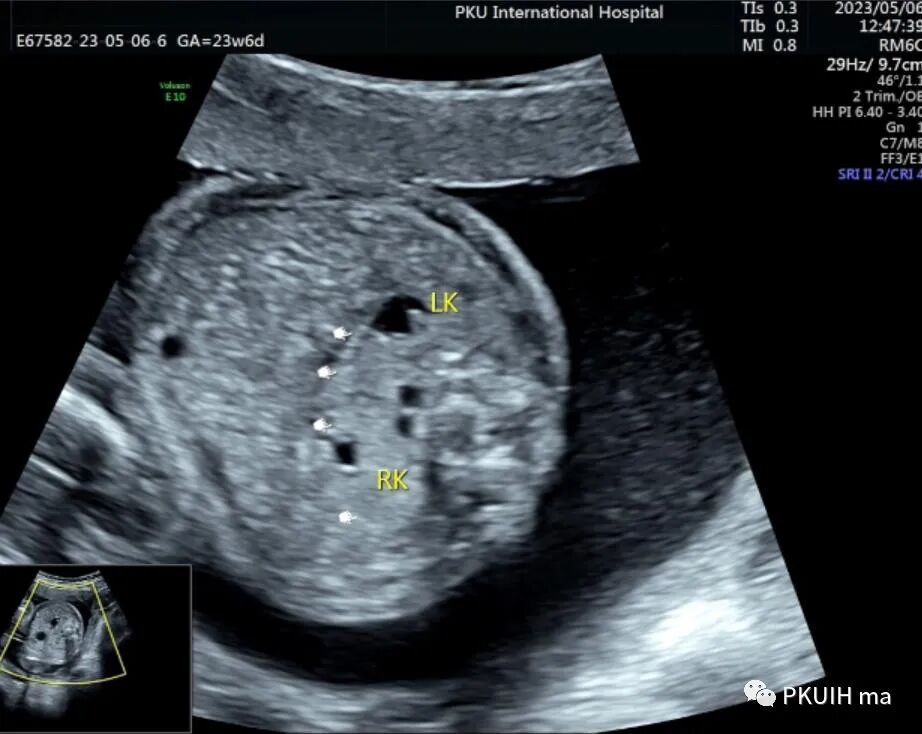

双肾横断面观察双肾盂轻微分离,肾门指向腹侧,呈倒“八”字征。(LK:左肾,RK:右肾)